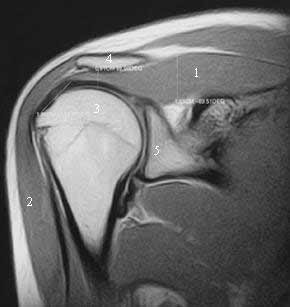

Магнитно-резонансная картина состояния ротаторной манжеты здорового плечевого сустава.

Рис. 1. МР томограмма правого плечевого сустава. Корональный срез. Показано измерение величины субакромиального пространства (0, 81 см) и вычисление отношения наиболее широкой части брюшка надостной мышцы к длине сухожильной ее части - корональный коэффициент (КК=0, 989).

1-надостная мышца

2-дельтовидная мышца

3-головка плечевой кости

4-акромиальный отросток лопатки

5-суставная впадина лопатки